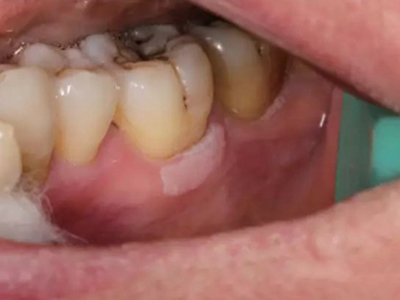

牙龈

白斑

口腔白斑病牙龈块状白斑图

口腔白斑病表现为牙龈处有稍高出黏膜表面的白色斑块,不粗糙、柔软,周围黏膜正常,患者无明显的自觉症状,偶尔有粗糙感或木涩感。